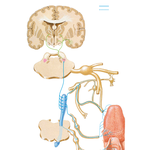

• Taste Pathways: Schema

146. Taste Pathways: Schema